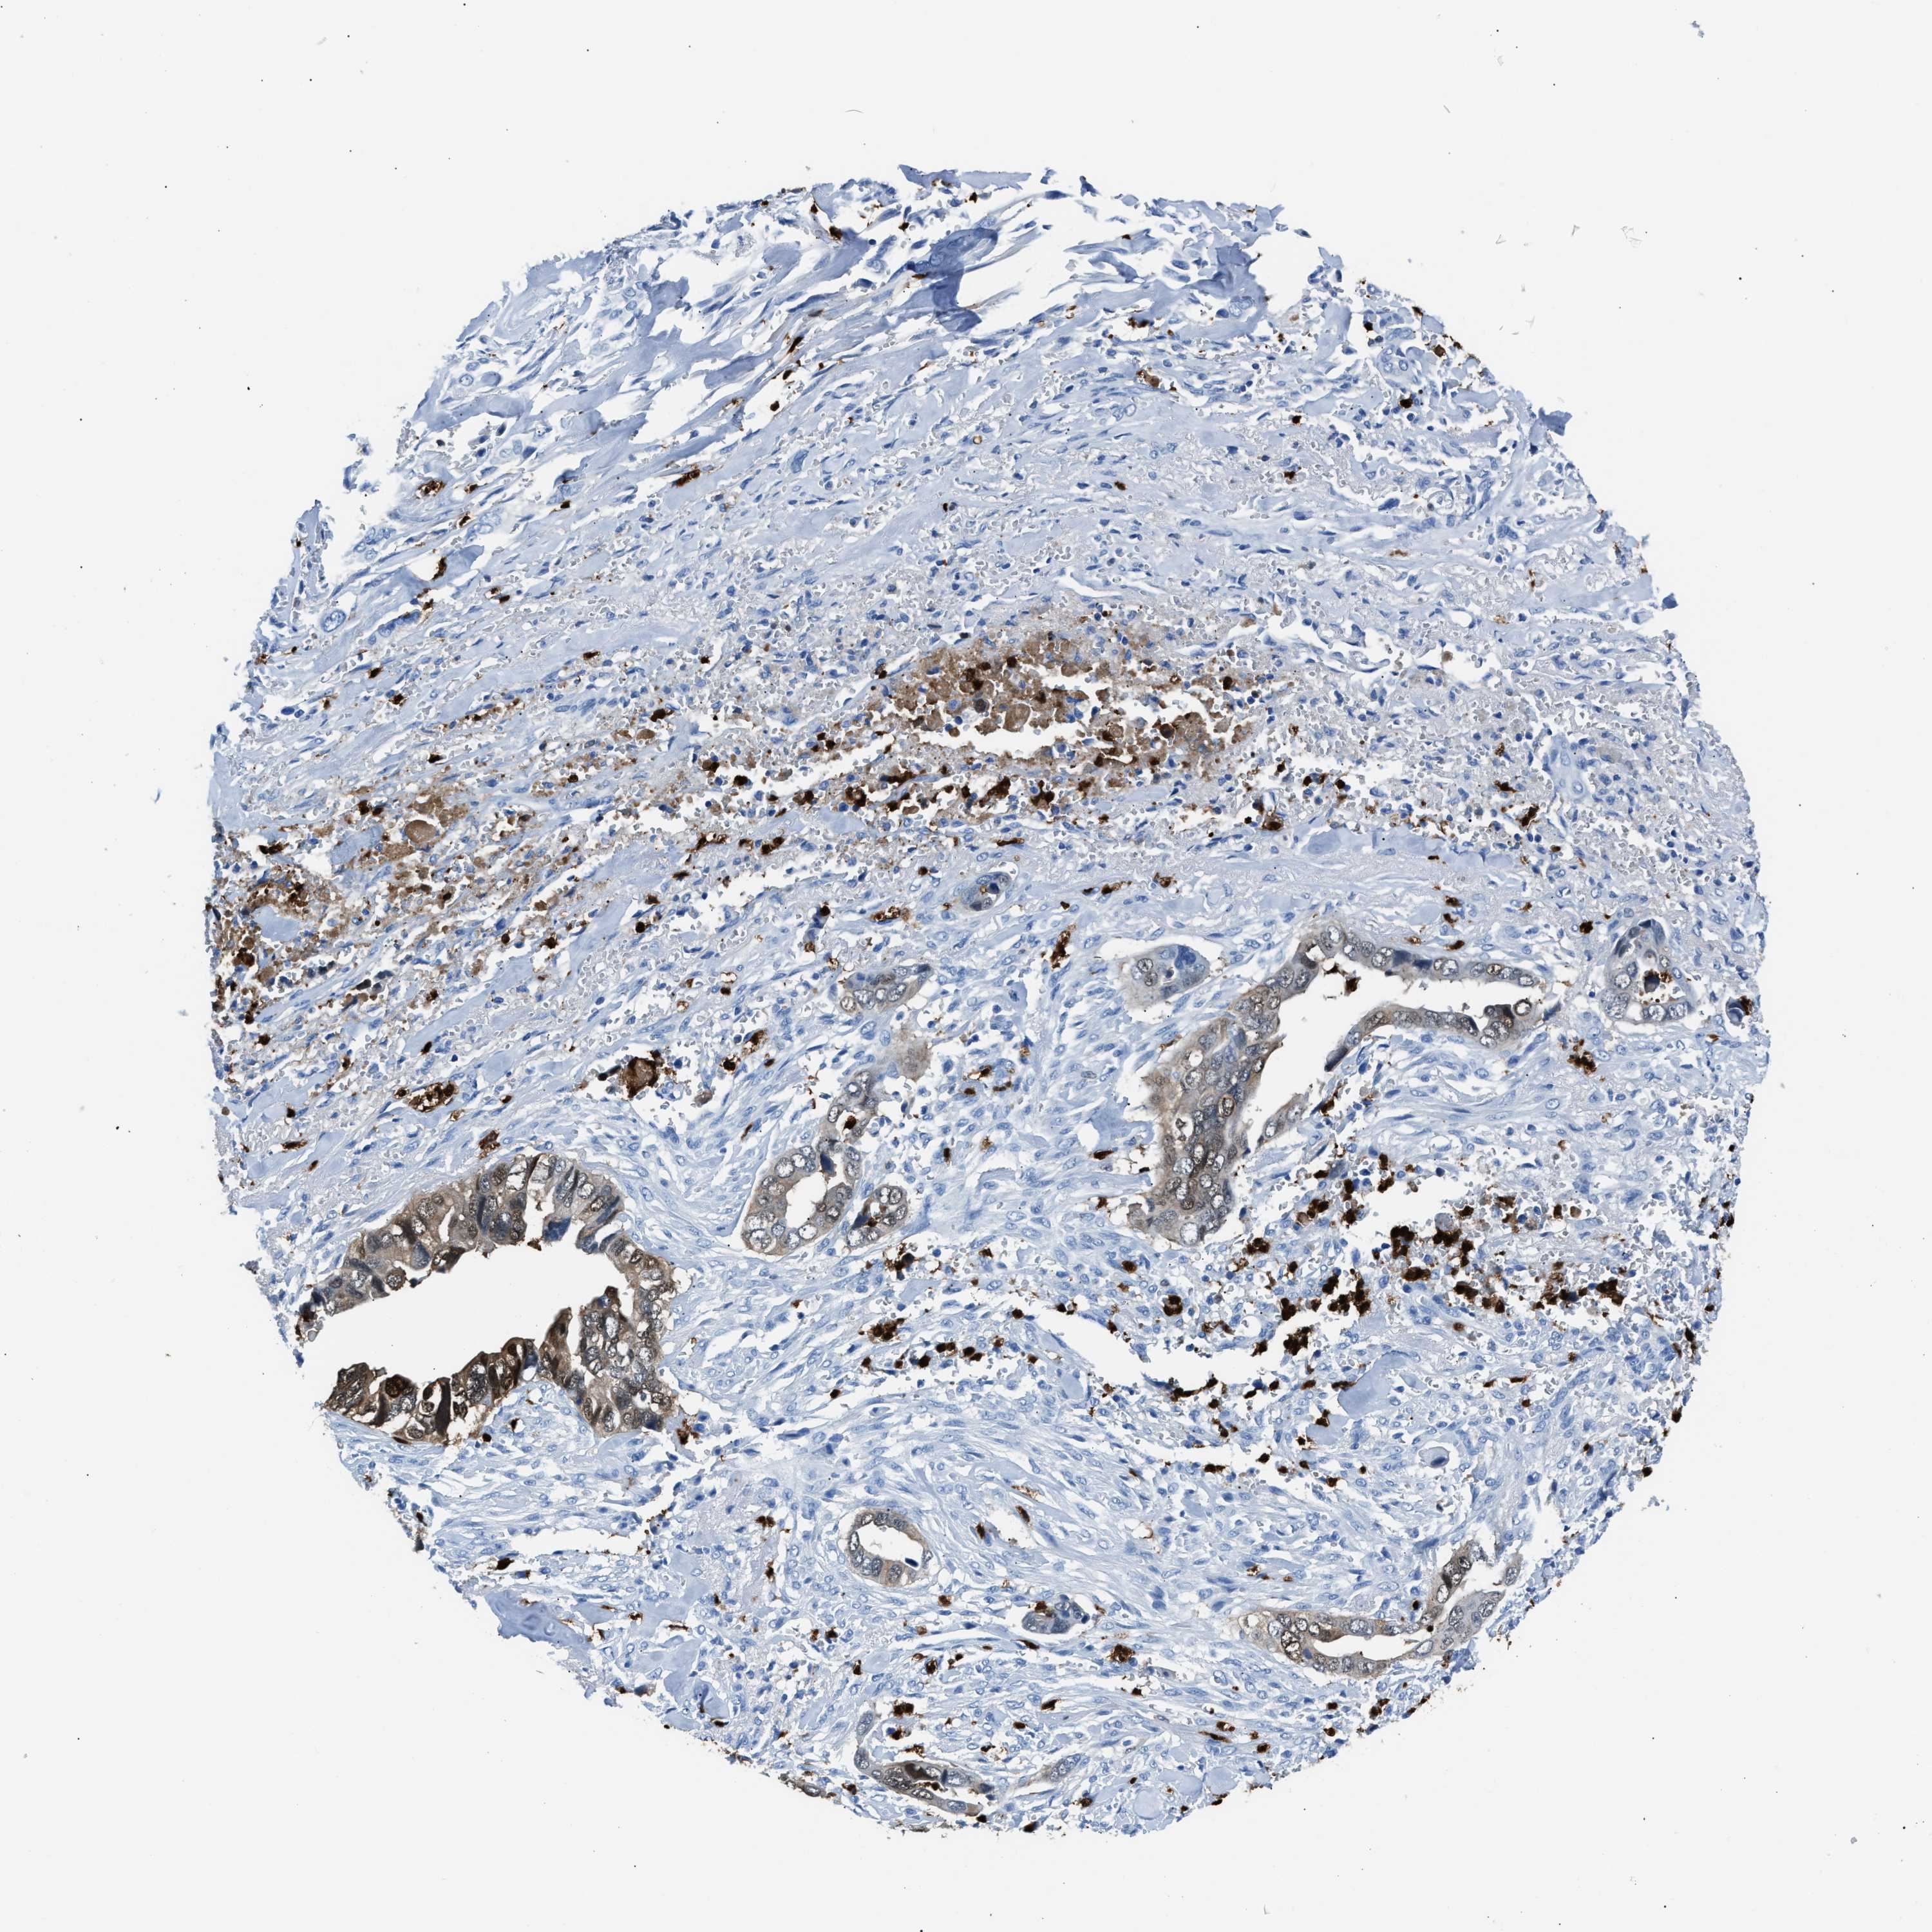

LIVER CANCER - Protein expressioni

A mouse-over function shows sample information and annotation data. Click on an image to view it in a full screen mode. Samples can be filtered based on level of antibody staining by selecting one or several of the following categories: high, medium, low and not detected. The assay and annotation is described here.

Note that samples used for immunohistochemistry by the Human Protein Atlas do not correspond to samples in the TCGA dataset.

Antibody stainingi

Antibody staining in the annotated cell types in the current human tissue is reported as not detected, low, medium, or high, based on conventional immunohistochemistry profiling in selected tissues. This score is based on the combination of the staining intensity and fraction of stained cells.

Each image is clickable and will lead to virtual microscopy that enables deeper exploration of all samples and also displays staining intensity scores, fraction scores and subcellular localization as well as patient and tissue information for each sample.

Antibody HPA019502

Staining

High

Medium

Low

Not detected

Intensity

Strong

Moderate

Weak

Negative

Quantity

>75%

75%-25%

<25%

None

Location

Nuclear

Cytoplasmic/membranous

Cytoplasmic/membranous,nuclear

Cholangiocarcinoma

Carcinoma, Hepatocellular, NOS